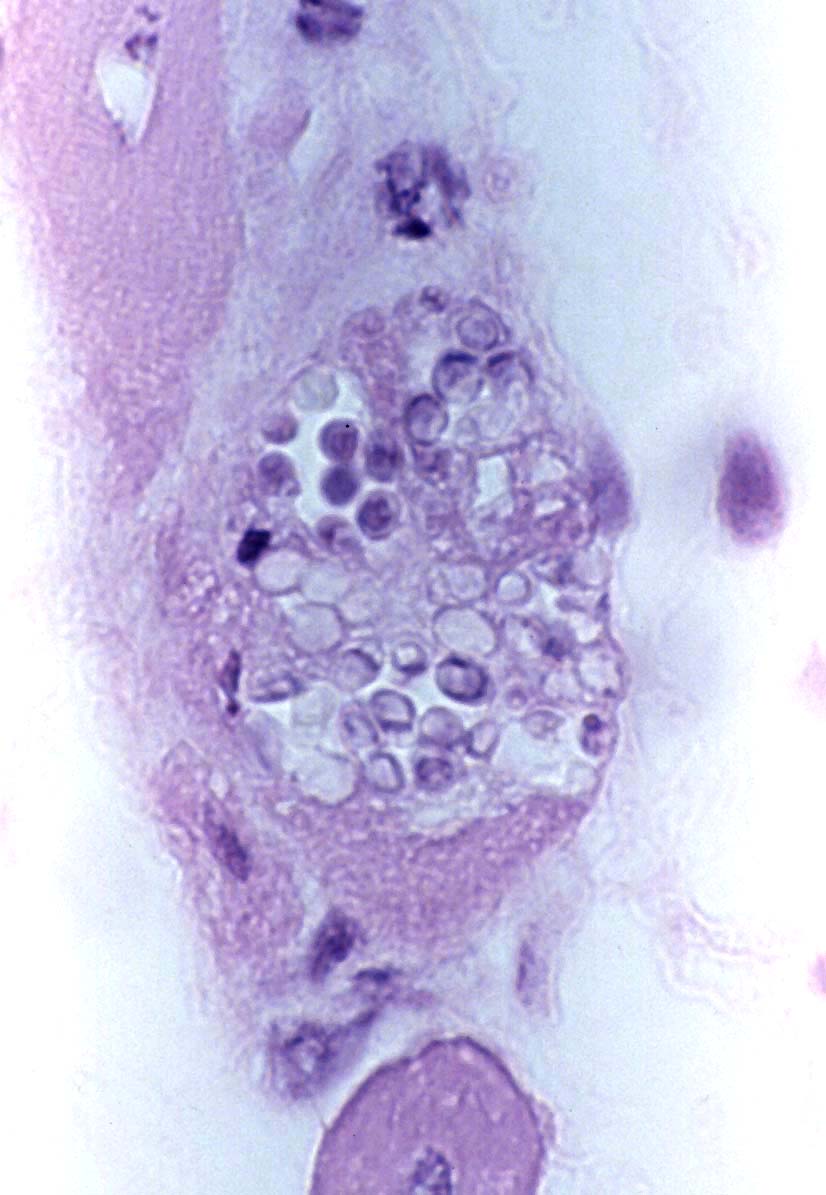

Unknown microsporidian |